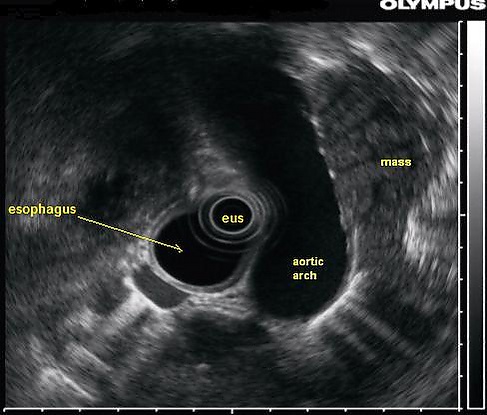

Эндосоногра́фия (эндоскопи́ческий ультразву́к) — комбинированное исследование, при котором ультразвуковой датчик с помощью эндоскопа вводится в полость пищевода, желудка или кишечника с целью получить более чёткие изображения глубоко расположенных органов.[1] Может сочетаться с допплерографией для оценки кровотока в сосудах, а также с тонкоигольной аспирационной биопсией[2].

В исследованиях Старкова, Солодиноной и др. (2009) диагностическая точность эндосонографии в выявлении плотных опухолей поджелудочной железы составила 94,8 %.[1] Метод является лидирующим в выявлении опухолей сосочка двенадцатиперстной кишки, где его диагностическая точность составляет 97,2 %, что гораздо выше других методов, включая дуоденоскопию.

В диагностике камней желчных протоков (холедохолитиаз) эндосонография с точностью 90,2 % позволяет выявлять конкременты диаметром 3 мм и менее, превышая таким образом, возможности обычного УЗИ и магнитно-резонансной холангиопанкреатографии. Улучшить диагностическую точность метода эндосонографии позволяют такие современные методы диагностики, как тонкоигольная пункция, допплеровское картирование и эластография.